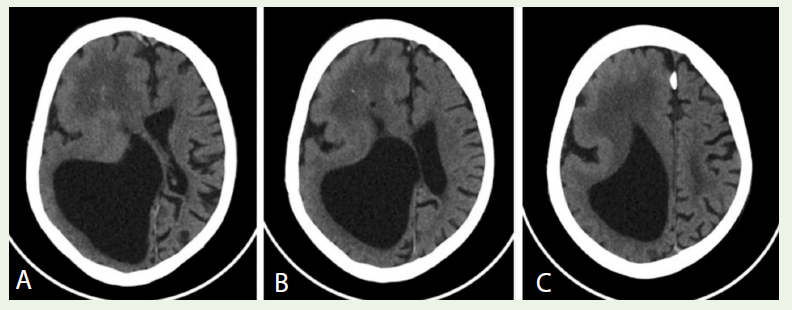

Case 2: A 15-year-old boy with infantile spasms and left hemiparesis had right hemispheric ventriculomegaly and cortical dysplasia on CT [Figure 2A-C], indicating hemimegalencephaly.

Imaging findings: Non-contrast CT of the head revealed marked

asymmetry of the cerebral hemispheres. The right hemisphere

was enlarged with severe dilation of the right lateral ventricle

(monoventricle) due to blockage at the foramen of Monro and

leward midline shi [Figure 2A]. The right occipital and temporal

cortex appeared thinned and effaced. The right hemisphere showed

diuse low-density white matter and scattered areas of calcification.

The cortical sulci in the right frontal and parietal lobes were effaced

and the gyri were abnormally enlarged [Figure 2B-C], suggestive of

diffuse pachygyria.

Diagnosis: These imaging features—unilateral hemispheric

enlargement with ventriculomegaly, cortical malformation, and

contralateral shift—are diagnostic of right-sided hemimegalencephaly.

Figure 2: A: Axial CT image showing an enlarged right lateral ventricle (monoventricle) with midline shift to the left, indicating obstruction at the right foramen of Monro. B: Axial CT image showing di昀昀use low density of right hemispheric white matter and scattered calcifed foci in the right frontal lobe. C: Axial CT image showing effaced cortical sulci and enlarged gyri in the right frontal and parietal lobes (Pachygyria).